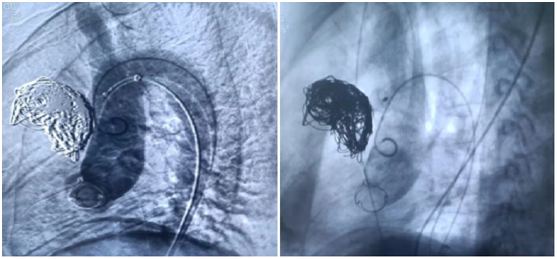

假性動(dòng)脈瘤自愈者很少,傳統(tǒng)的治療方法是手術(shù),血管內(nèi)治療應(yīng)用可脫球囊、鎢絲螺旋圈閉塞動(dòng)脈瘤腔、載瘤動(dòng)脈或用彈簧圈閉塞載瘤動(dòng)脈;對(duì)鄰近鎖骨下動(dòng)脈的頸動(dòng)脈巨大假性動(dòng)脈瘤,單用手術(shù)或血管內(nèi)治療有較大困難者,用氣囊導(dǎo)管經(jīng)血管腔內(nèi)暫時(shí)阻斷載瘤動(dòng)脈,再配合手術(shù)治療;對(duì)比較表淺的頸外動(dòng)脈假性動(dòng)脈瘤,在確診后用穿刺針直接穿刺動(dòng)脈瘤,經(jīng)穿刺針?biāo)腿霃椈扇蜴u絲微彈簧圈閉塞動(dòng)脈瘤。

術(shù)中造影顯示動(dòng)脈瘤(箭頭所示),用彈簧圈填塞